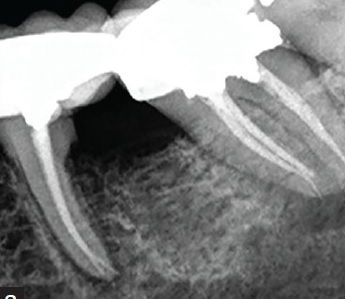

Salvaging a compromised tooth by an inter-disciplinary approach - A case report in 6 th national conference of Indian society of Prosthodontics- Restorative-Periodontics(ISPRP)